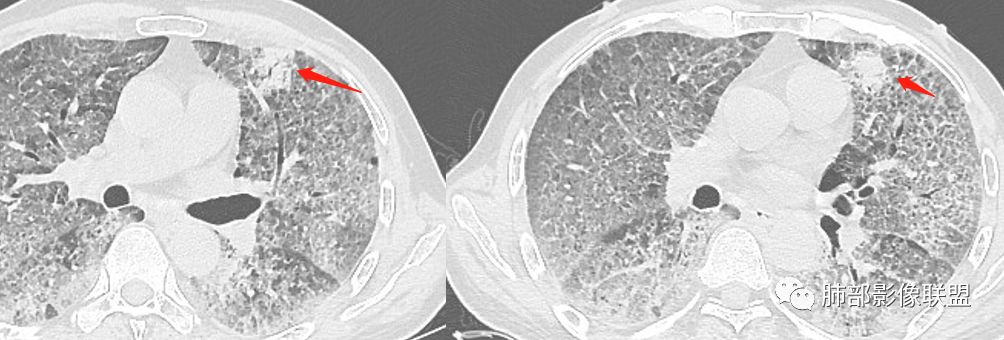

八爪:弥漫分布磨玻璃密度影,小叶间隔增厚,典型铺路石征,考虑PAP伴发感染性病变,鉴别特发性间质性肺炎,弥漫性腺癌,建议支气管灌洗;左肺上叶舌段不规则团片状阴影,显示不清,密切随访

小景:双肺弥漫磨玻璃影,小叶间隔增厚,呈碎石路征。患者粉尘接触史,考虑PAP。左肺舌段病灶,抗感染无吸收,腺癌待排。

左上叶斑片状高密度影

3、左上叶斑片状高密度影:感染?肿瘤?